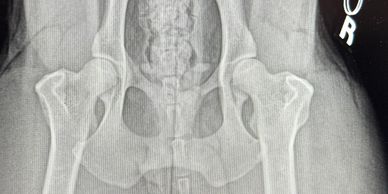

All breeding dogs undergo X-ray evaluation of their elbows and hips via OFA or PennHip.Veterinary Evaluation of Patellar Luxation. Results registered with OFA. Any dogs not passing evaluation will not be bred.